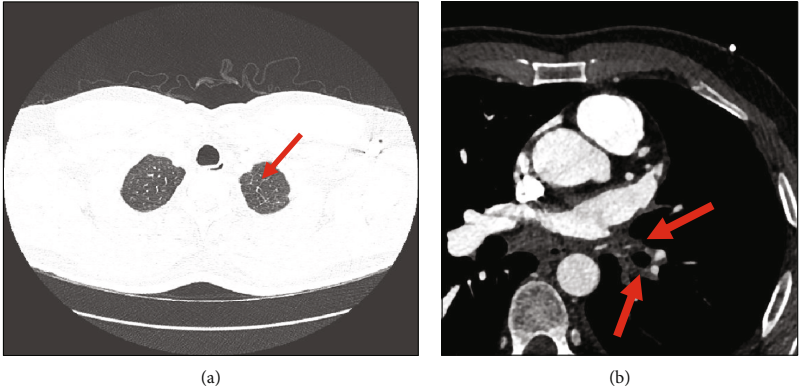

图2. CTPA:(a)单侧肺水肿伴小叶间隔增厚(箭头);(b)Lt.PVsO(箭头)。CTPA:计算机断层扫描肺血管造影;Lt.PVsO:左肺静脉阻塞

尽管如此,患者的咯血仍然持续。接下来进行了对比增强CTPA,显示单侧左肺静脉阻塞的特征,左上下肺静脉未见,均为闭塞,很可能由先前的消融术导致(如图2a,b)。除此之外,患者还接受了冠状动脉CTA检查,结果显示右上、下肺静脉造影清晰;但是,在动脉期左上肺静脉和下肺静脉均不可见(图3)。冠状动脉CTA的这些发现与左肺静脉阻塞的CTPA检查结果一致。患者还进行了一项肺灌注研究,结果显示在所有灌注视图中,左肺野均无灌注。在通气图像中,左肺通气良好,但低于右肺(图4)。支气管镜检查报告正常(无出血)。